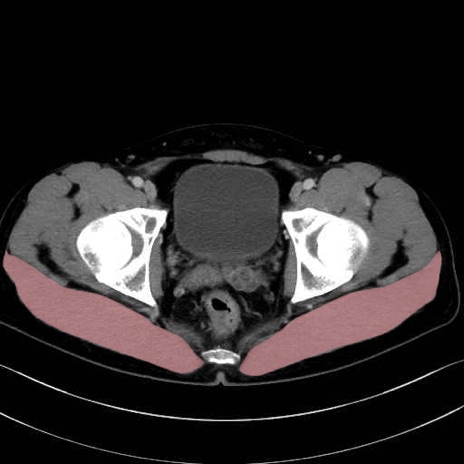

3. 殿部の筋肉(表層・中層・深層)

大殿筋 (Gluteus maximus)